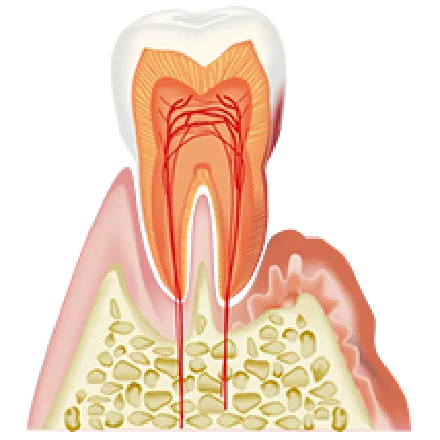

進行中度

腫れと、歯と歯茎との隙間や

歯磨きの時の出血が見られる